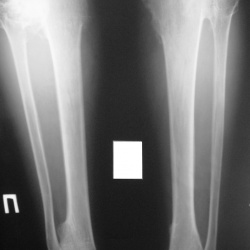

14.04.2011 - 18:28

Пациент 19 лет упал , ушиб правое колено . Мне не понятны кистообразные изменения в правой большеберцовой и в левой малоберцовой кости ? И ещё , маленькие тенюшечки во внутренней...